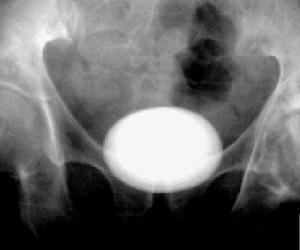

1.膀胱結石的診斷可根據病史中有排尿時尿流中斷,尿末劇痛和血尿等典型症狀。查體雙手觸診有時可觸及到結

膀胱結石2.尿道結石的診斷

1.B超檢查能顯示結石聲影,可同時發現前列腺增生。

2.X線檢查腹部平片絕大多數結石可顯影,並同時注意有否腎輸尿管結石。必要時可做尿路造影以了解尿路情況。